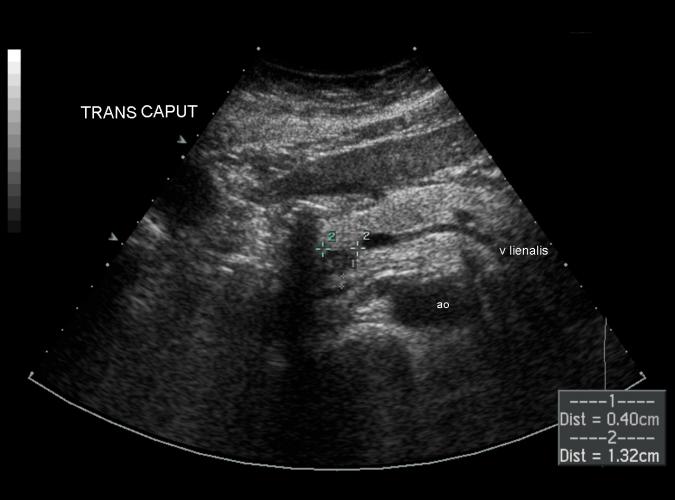

Trans.caput pancreas med liten lågekogen tumör. PAD adenocarcinom . Whipple op. Se long.bild 7b.